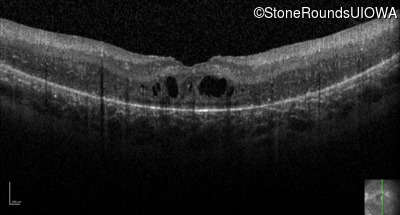

Optical Coherence Tomography - Left - 20/125 +2

Exemplar / OCT Stack